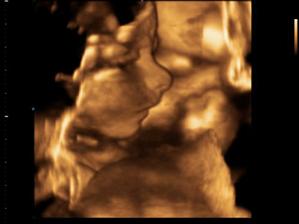

tak to jsou mé první testíky po ivf, je to 9 a 10 den, další testík je 13 den a dnes mi taky bylo potvrzeno těhotenství z krve, hodnota HCG je 678.

Kacatko